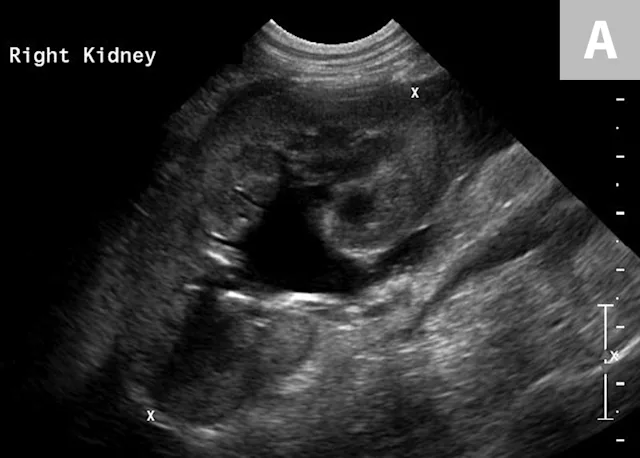

Clinical signs associated with ureteral calculi may range from chronic non-specific signs to acute or chronic renal failure. The presence of hydronephrosis can be highly suggestive of a ureteral obstruction (Figure 6).

FIGURE 6A

Mild to moderate right hydronephrosis and proximal ureteral dilation in a Dalmatian.